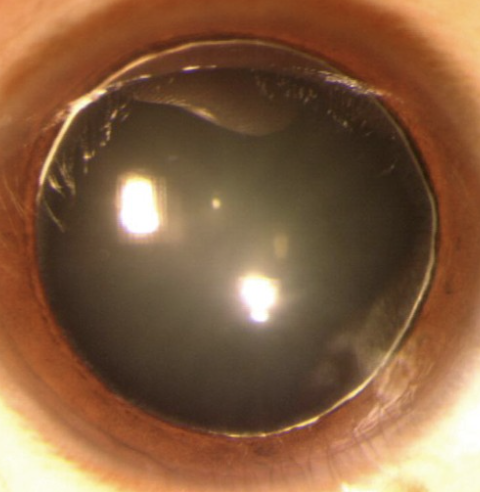

Hypopyon

Abnormal findings for Iris

Condition involving inflammatory cells in anterior chamber of eyes

Accumulation of white blood cells that form a whitish layer of fluid in the lower portion of the eye’s anterior chamber (front part); infection of internal eye.